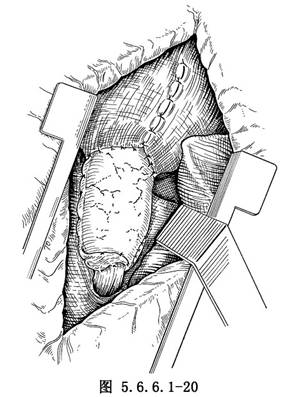

必须注意此切线尽量与胃体纵轴垂直,使大弯侧的切缘两边尽量接近90°,否则在胃端切口封闭后大弯侧将形成一个牛角形的管,直接影响血液供应。胃端在缝合的外侧再用细丝线间断缝合一层。将胃底贲门连同肿瘤及食管下端一并用纱垫包裹提至胸腔,在胃体上另作切口,在肿瘤上方3~4cm处与食管作吻合。如果不使用胃肠缝合器,可用直钳夹住胃体,在钳夹处的远侧胃大弯与小弯各作一牵引缝线,紧贴直钳远侧切开胃壁,用细丝线间断内翻缝合,将胃黏膜翻向胃内,外面再加一道浆肌层对浆肌层间断缝合,吻合完后缝合膈肌(图5.6.6.1-20),安放闭式引流管后关胸。